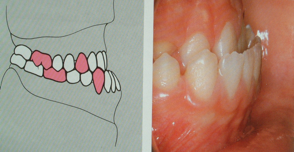

Morso incrociato

denti di un lato o di entrambi i lati combaciano in modo inverso rispetto alla norma (il molare superiore rimane più interno anziché più esterno all’inferiore). Il morso incrociato monolaterale è quasi sempre accompagnato da spostamento laterale di mandibola e mento verso il lato dell’incrocio. In tali casi è comune il sovraccarico della articolazione dello stesso lato della deviazione (il condilo viene compresso verso la cavità articolare) e una contrattura muscolare asimmetrica.

Nel morso incrociato bilaterale la simmetria può essere conservata ma l'occlusione patologica limita i movimenti funzionali della mandibola causando lo spasmo (contrazione) dei muscoli facciali.